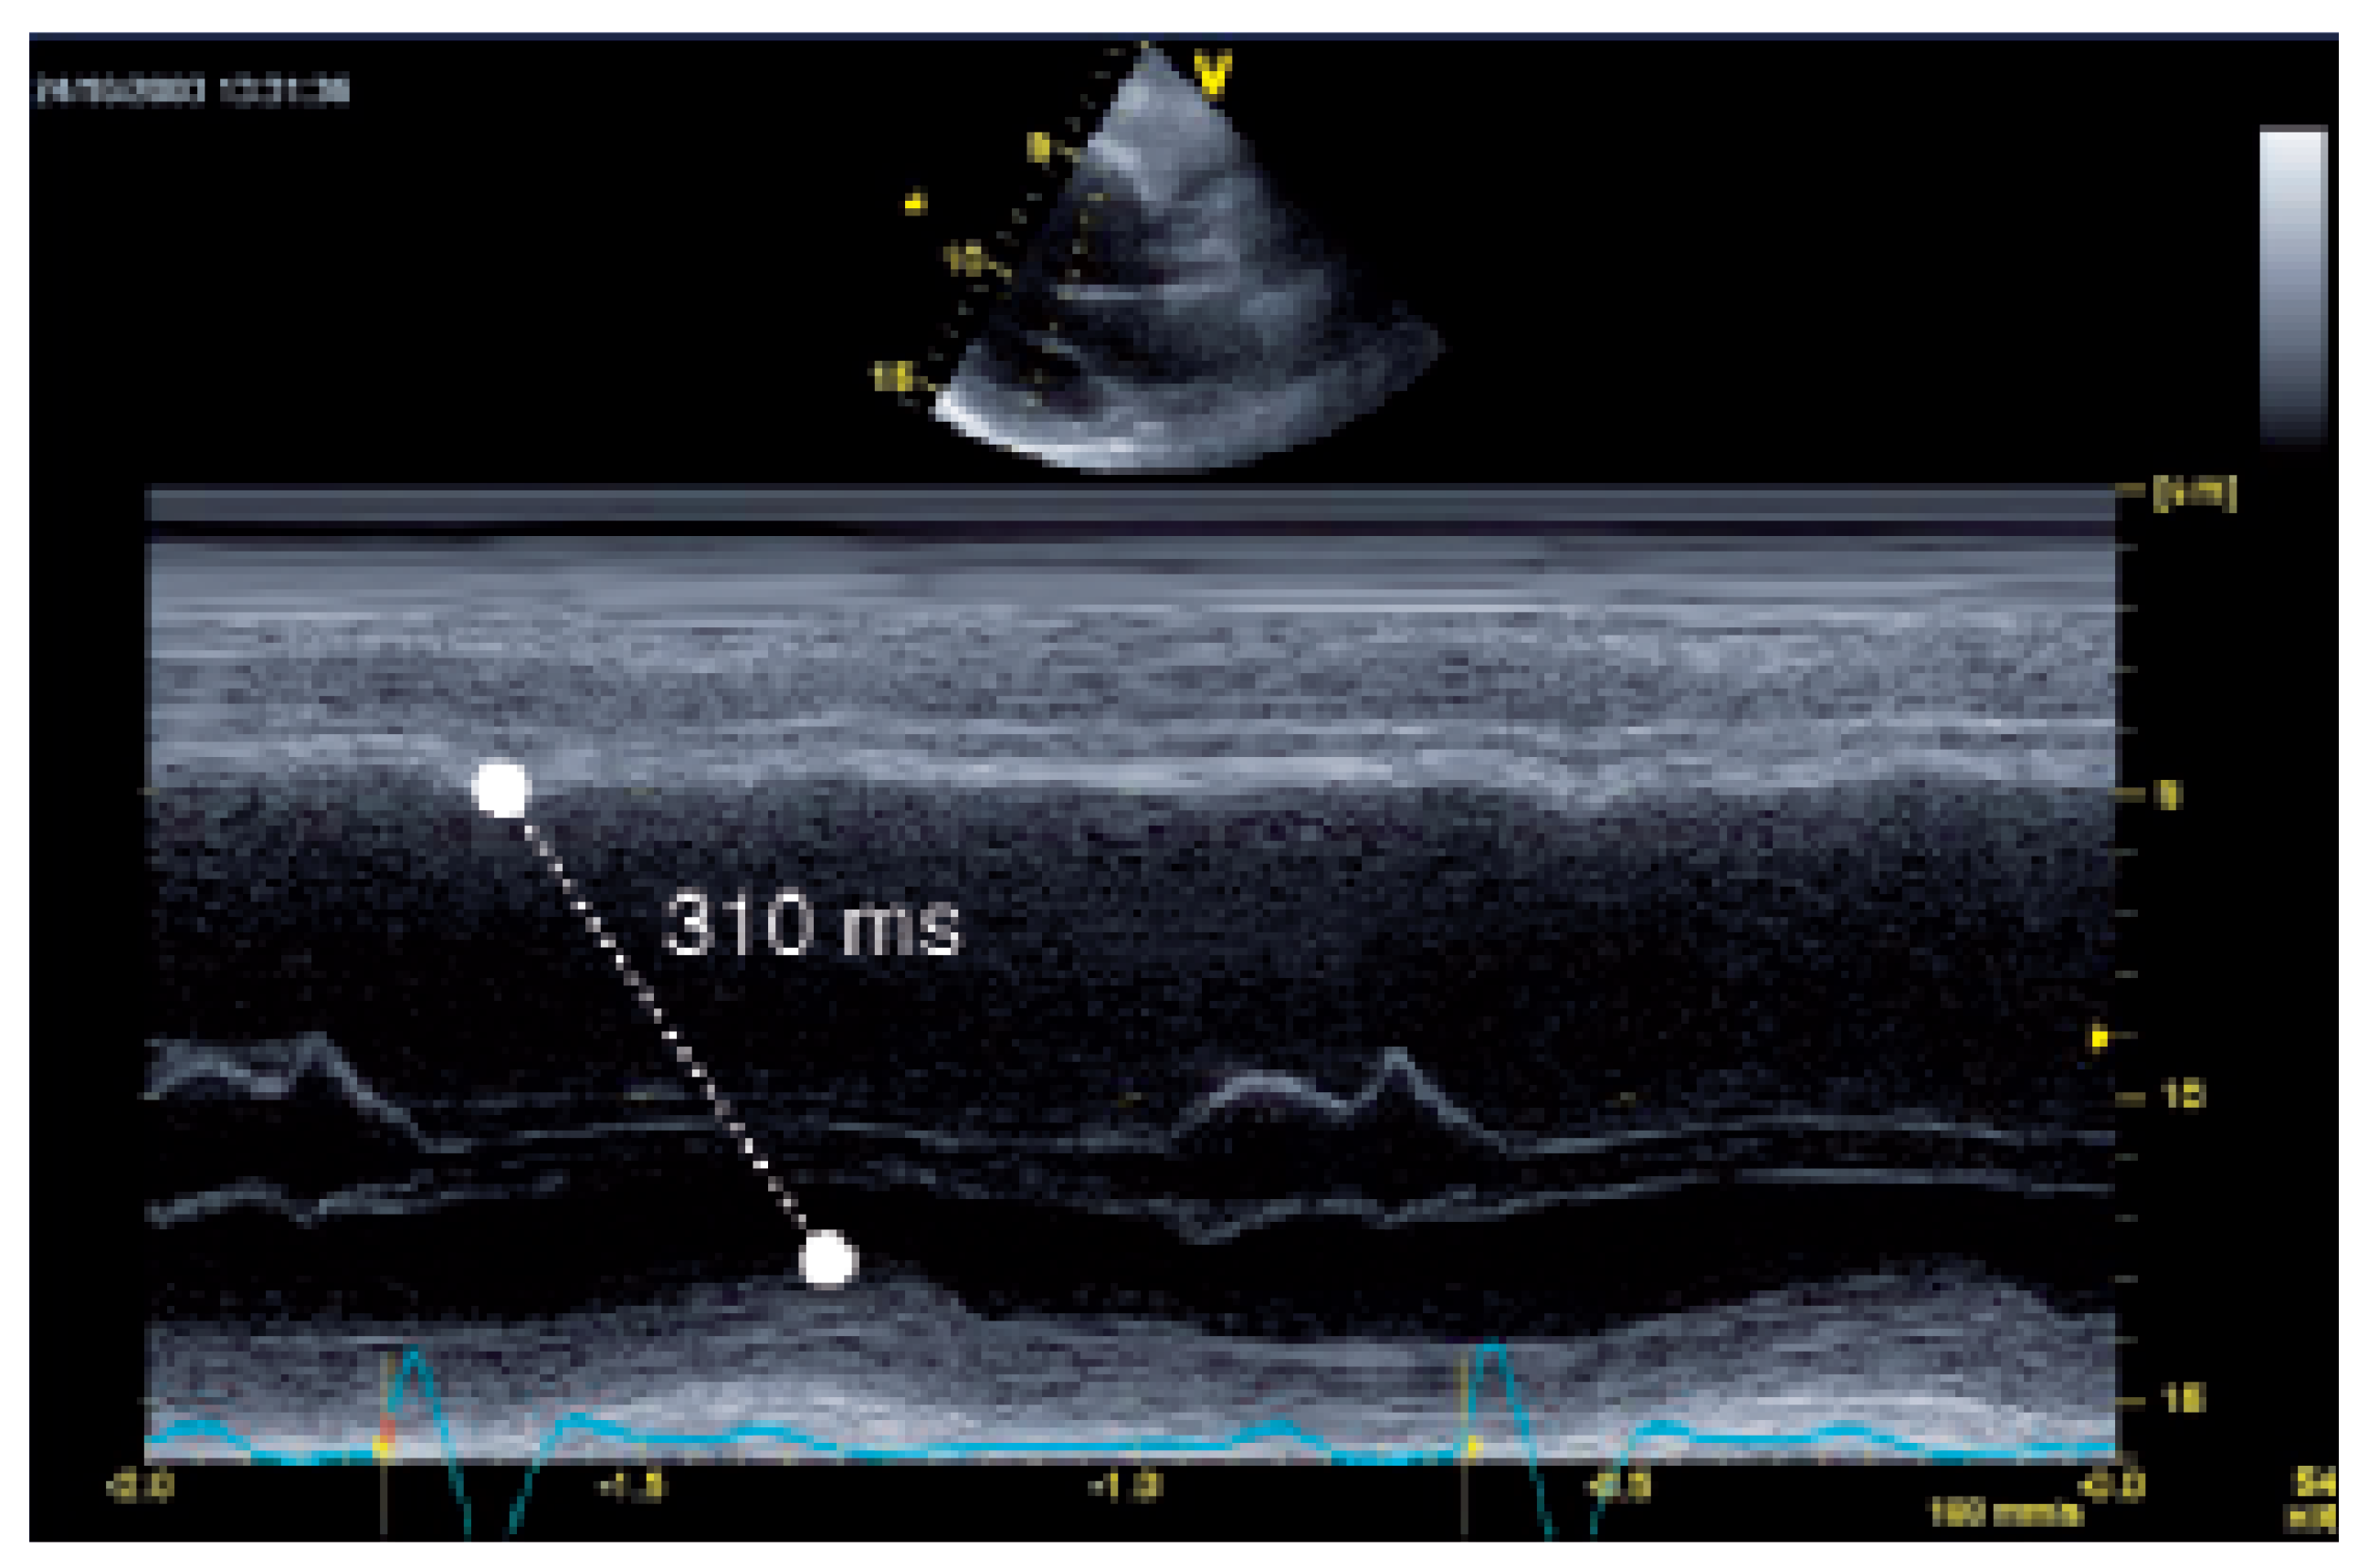

M-Mode